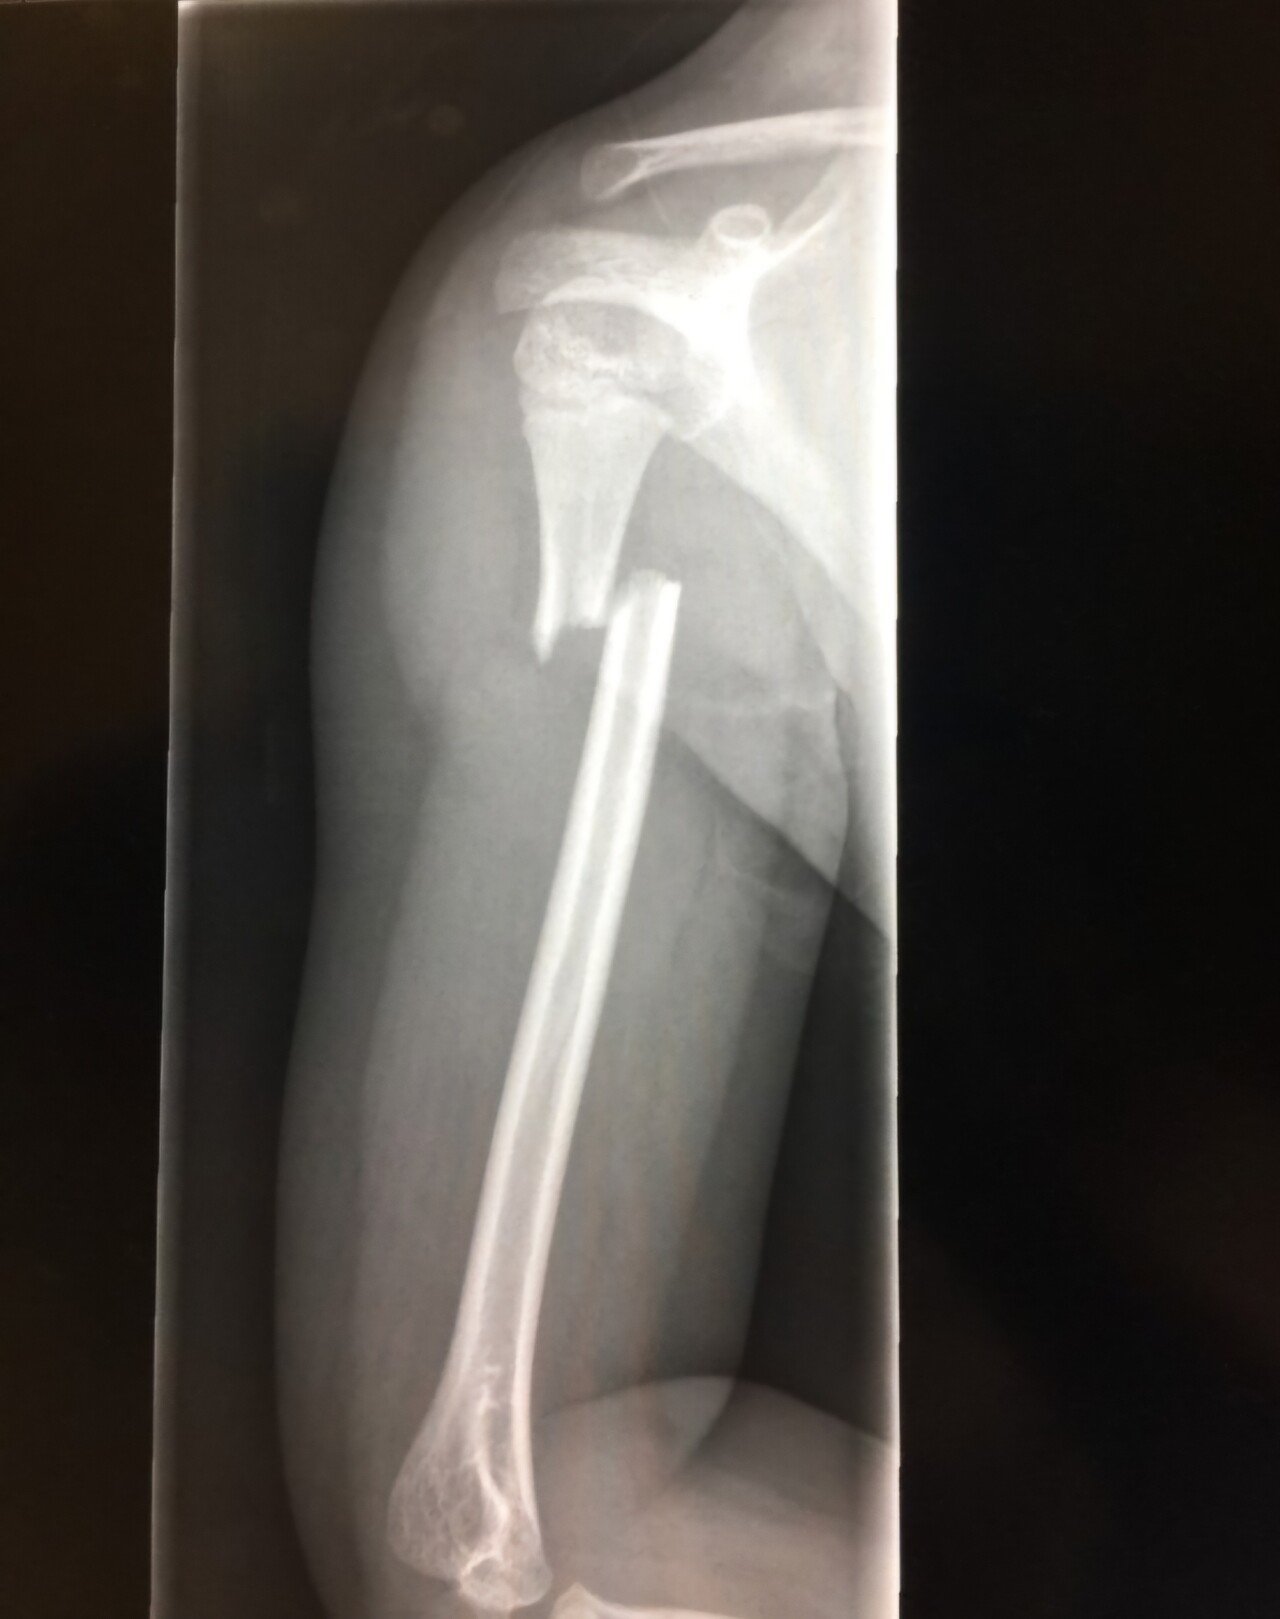

4년전에 사진 처럼 팔이 되버려서 팔수술하고 신경쪽 마비증상이 좀 남았는데, 그때는 별로 안심해서 남자는 군대가야지 하고 군대갔음.

그러다가 군대에서 열심히 뺑이치니깐 신경통이 아플정도로 심해져서 병원가보니 팔쪽 요골감각신경이 40% 운동신경이 72% 남았다더라.